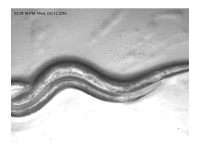

At the Laboratory of Applied Bioscience, my work focuses on utilizing Caenorhabditis elegans (C. elegans) as a model organism to assess the effects of plant-derived extracts and synthetic compounds. With its genetic simplicity, well-characterized biology, and relevance to higher organisms, C. elegans offers a powerful system for studying therapeutic potential and understanding mechanisms linked to health and disease.

This research aims to identify and characterize bioactive compounds that may contribute to novel pharmacological applications. By bridging experimental biology with modern analytical approaches, our work strengthens model organism research in Bangladesh and contributes to global scientific efforts in drug discovery and human health.

Figure: C. clegans